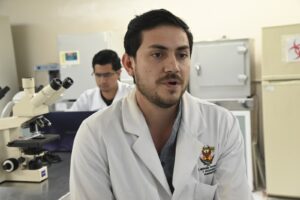

José Mario Atondo Pacheco, especialista e investigador quien labora en el laboratorio de Parasitología de la Facultad de Medicina Veterinaria y Zootecnia de la Universidad Autónoma de Sinaloa (UAS), explicó que son las misma manifestaciones clínicas que en los animales, donde el contagio se da de dos formas; las directas, que son convivir con personas con Sarna, pareja sexuales, entre otras, mientras que la forma indirecta es el uso de sábanas en los hoteles, el compartir ropa usada que no está desinfectada, toallas, entre otras formas.